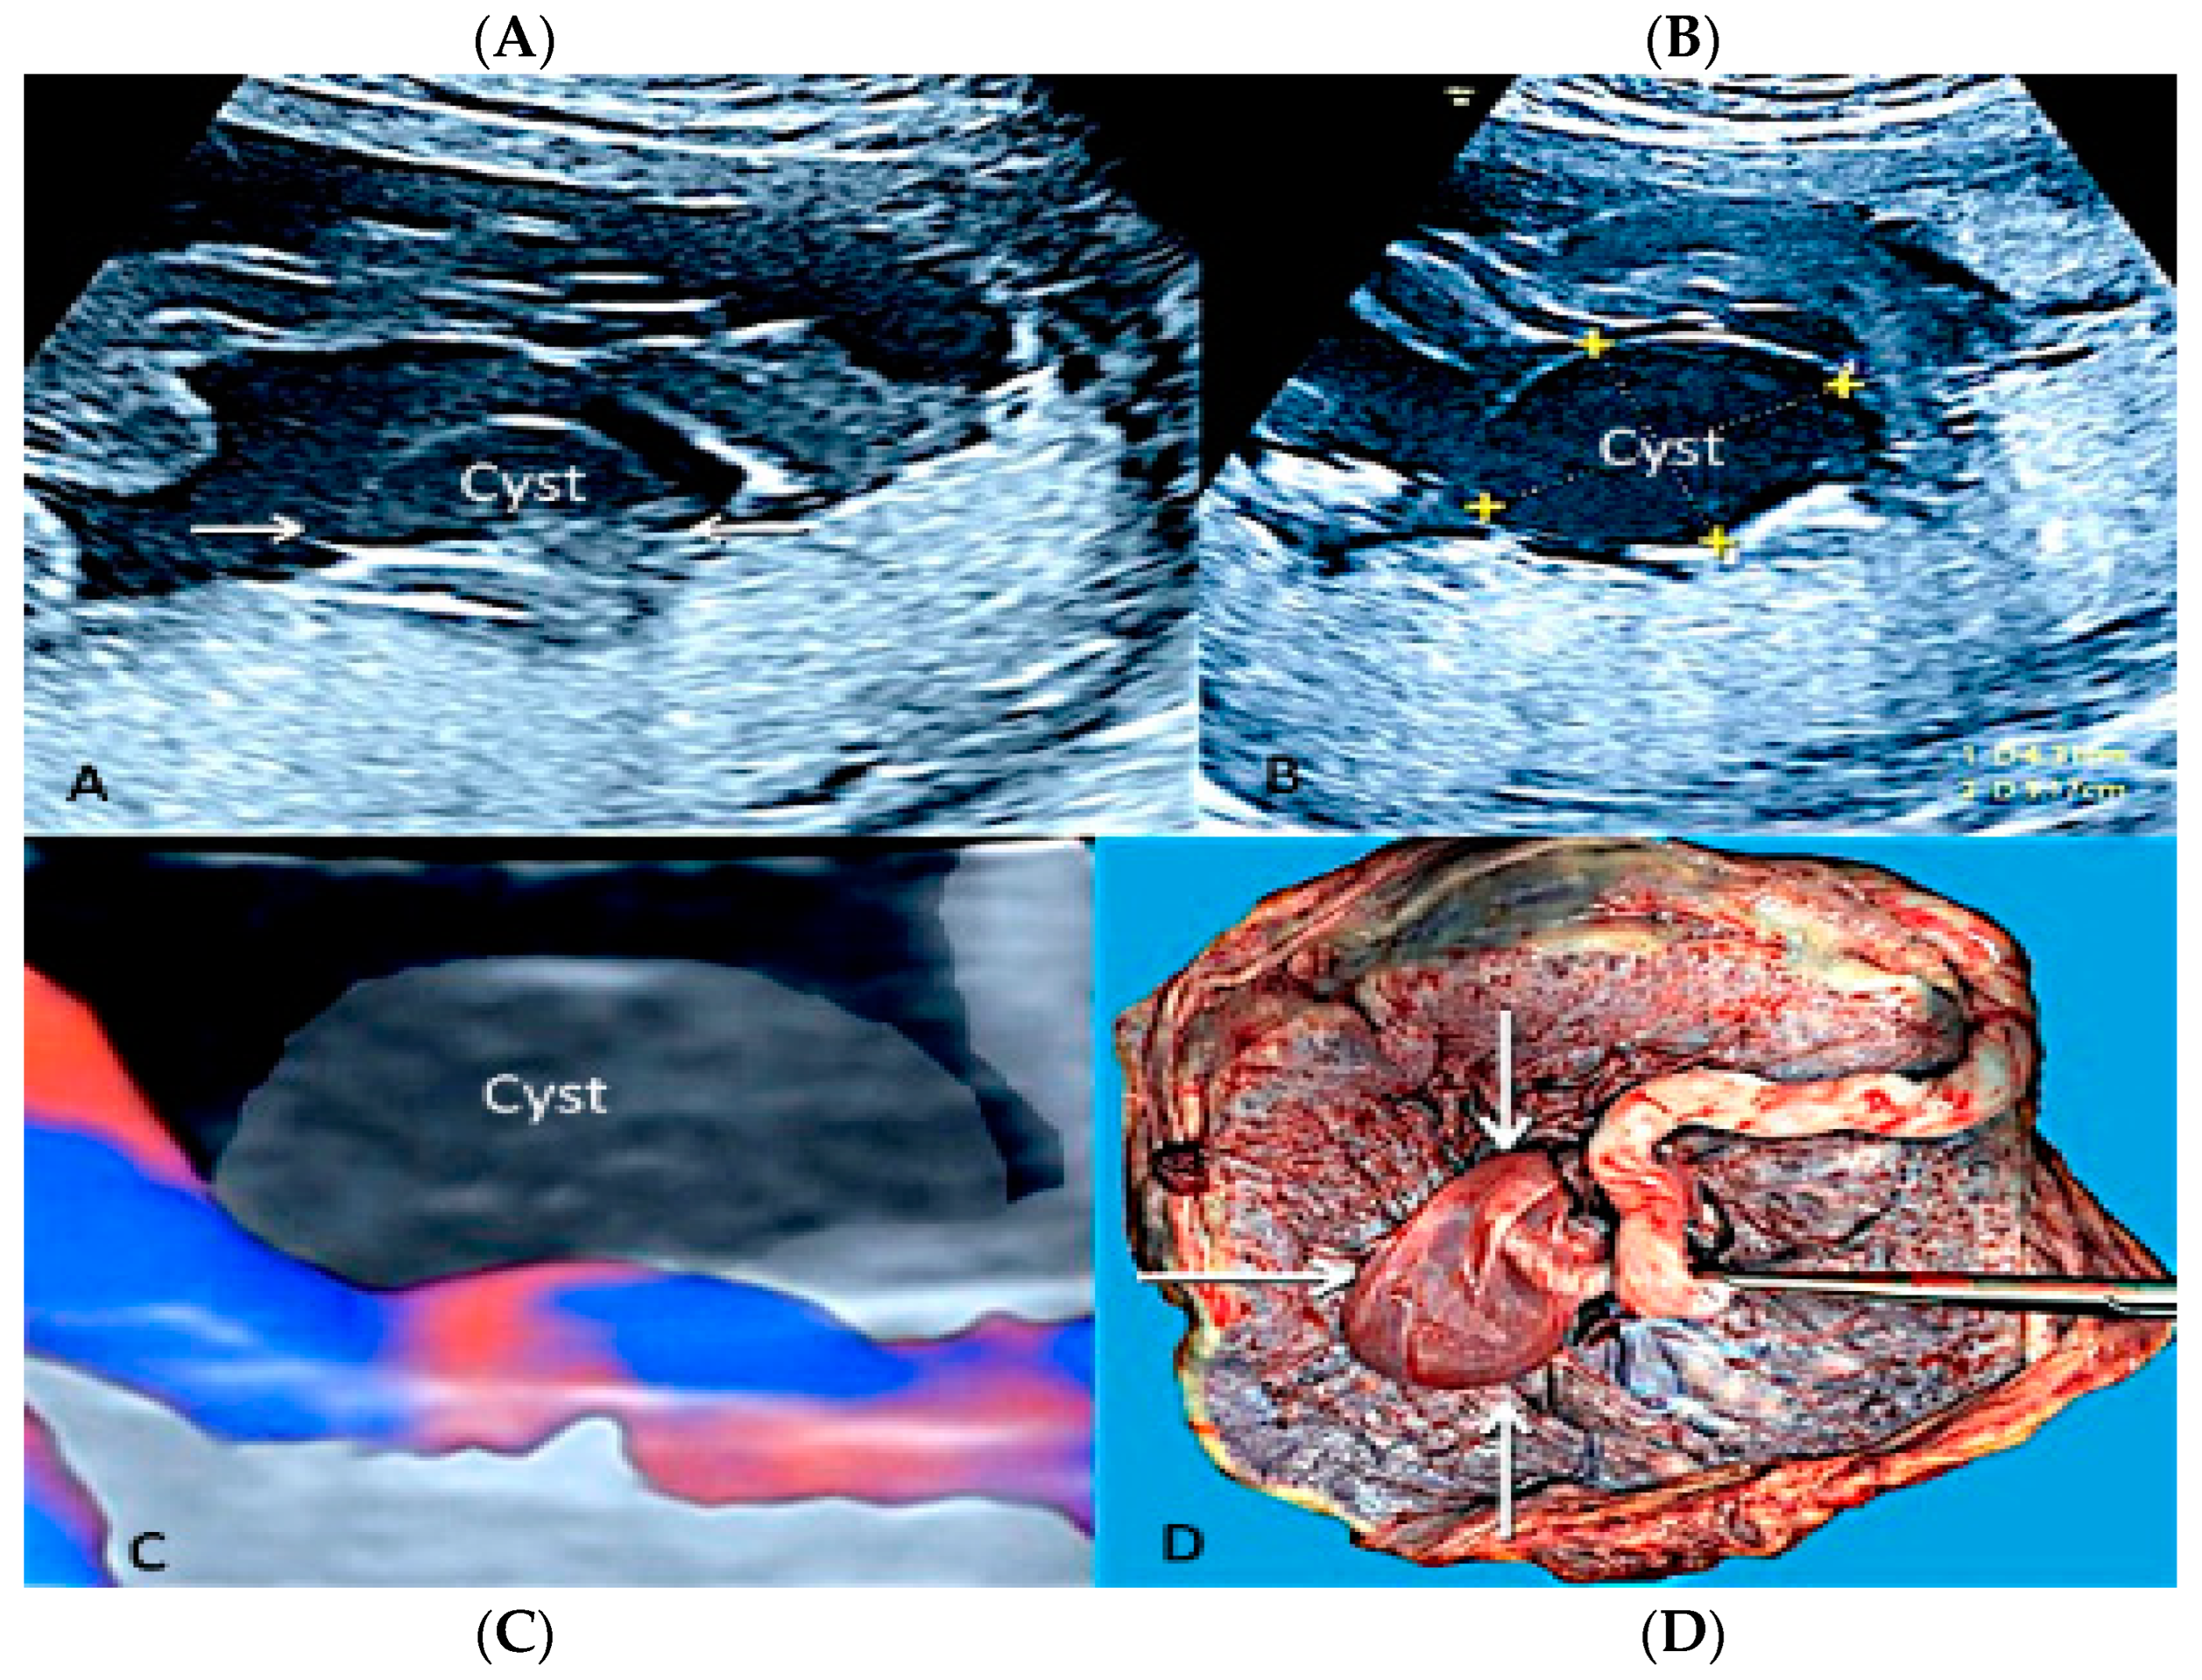

3.1.7. Membranous Placental Cysts

Membranous placental cysts, also known as “subchorionic cysts”, “chorionic cysts” or “membranous cysts” [42], are placental lesions formed by a deposit of fibrin in the subchorionic layers, forming a central cystic component. Brown et al. [43] have demonstrated that when the diameter of the cysts is greater than 4.5 cm, there is a high association with fetal growth restriction. On a grey-scale ultrasound evaluation, this type of placental disease resembles a chorioangioma and differential diagnosis is possible using color flow Doppler ultrasound, as subchorionic cysts have no flow [29] (Figure 14).

Figure 14.

Two-dimensional (A,B) and three-dimensional ultrasound with HD flow using “glass body” mode (C) showing chorionic plate cyst. It depicts an anechoic thin-walled structure on the fetal surface of the placenta near the cord insertion (arrows) (A,B) without internal vascularity (C). Pathologic correlation (arrows) (D).